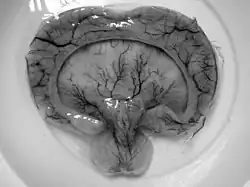

Gross pathology specimen from a case of alobar holoprosencephaly

Alobar

The most severe form of holoprosencephaly, this includes formation of synophthalmia (a single central eye), proboscis, and severe impairment.[3]